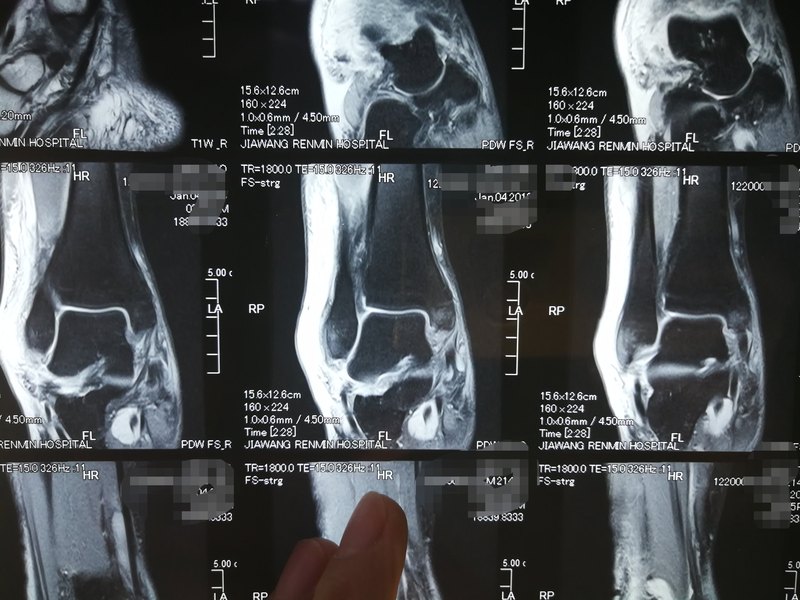

今天做的一例踝關(guān)節(jié)扭傷導(dǎo)致韌帶撕裂的病人。 術(shù)中見(jiàn)韌帶完全撕裂,給予縫合。 所以不要輕視踝關(guān)節(jié)扭傷,如果扭傷后出現(xiàn)明顯腫脹,且內(nèi)或者外踝尖部周?chē)忻黠@壓痛,建議行磁共振檢查,明確由于韌帶撕裂,出現(xiàn)撕裂,建議手術(shù)吻合,否則后期很容易出現(xiàn)踝關(guān)節(jié)扭 傷,伸直出現(xiàn)踝關(guān)節(jié)創(chuàng)傷性關(guān)節(jié)炎。